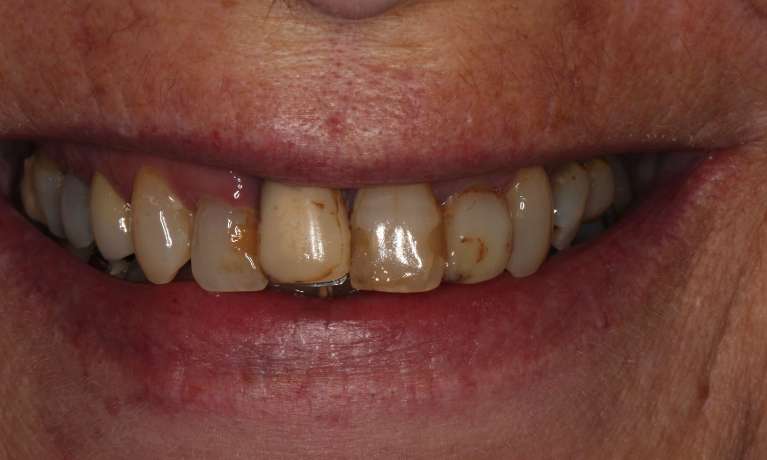

This adult patient had heavily restored discolored and defective upper front teeth. Their upper front four teeth were rejuvenated with new crowns to give the finished smile.